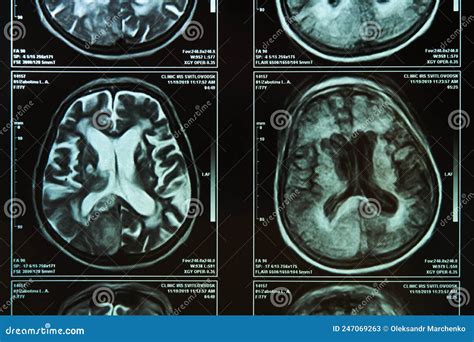

Medical imaging technology has revolutionized the way we understand human health, and among these diagnostic tools, Brain MRI Images stand out as the gold standard for visualizing the complex architecture of the central nervous system. Magnetic Resonance Imaging (MRI) provides incredibly detailed, non-invasive views of the brain's internal structures, allowing medical professionals to identify anomalies, track the progression of diseases, and plan surgical interventions with pinpoint accuracy. Unlike X-rays or CT scans, which rely on ionizing radiation, MRI machines utilize powerful magnetic fields and radio waves to generate sophisticated, multi-planar cross-sections of brain tissue.

This technology is essential for distinguishing between various types of tissues, such as gray matter, white matter, and cerebrospinal fluid. By manipulating the timing of the radiofrequency pulses—a process referred to as adjusting pulse sequences—radiologists can emphasize different pathological features, making it easier to spot tumors, lesions, or inflammatory processes.

The utility of Brain MRI Images extends across numerous neurological specialties. Because these images provide superior soft-tissue contrast, they are the preferred modality for identifying issues that other imaging techniques might miss. Clinicians rely on these scans to diagnose and monitor a variety of conditions, including:

• Tumors and Neoplasms: Identifying the precise location, size, and type of brain tumors.

• Neurodegenerative Diseases: Detecting patterns of brain atrophy associated with Alzheimer’s, Parkinson’s, and multiple sclerosis.

• Cerebrovascular Issues: Assessing the impact of strokes, identifying aneurysms, or evaluating blood flow irregularities.

Once the images are acquired, they are processed and sent to a radiologist. These specialists are trained to meticulously examine the Brain MRI Images, looking for subtle deviations from normal anatomy. They look for signals that are “hyperintense” (bright) or “hypointense” (dark) on the scan, which often indicate different types of pathology. The radiologist then synthesizes these findings into a comprehensive report for the referring physician, who uses the data to determine the next steps in treatment or management.